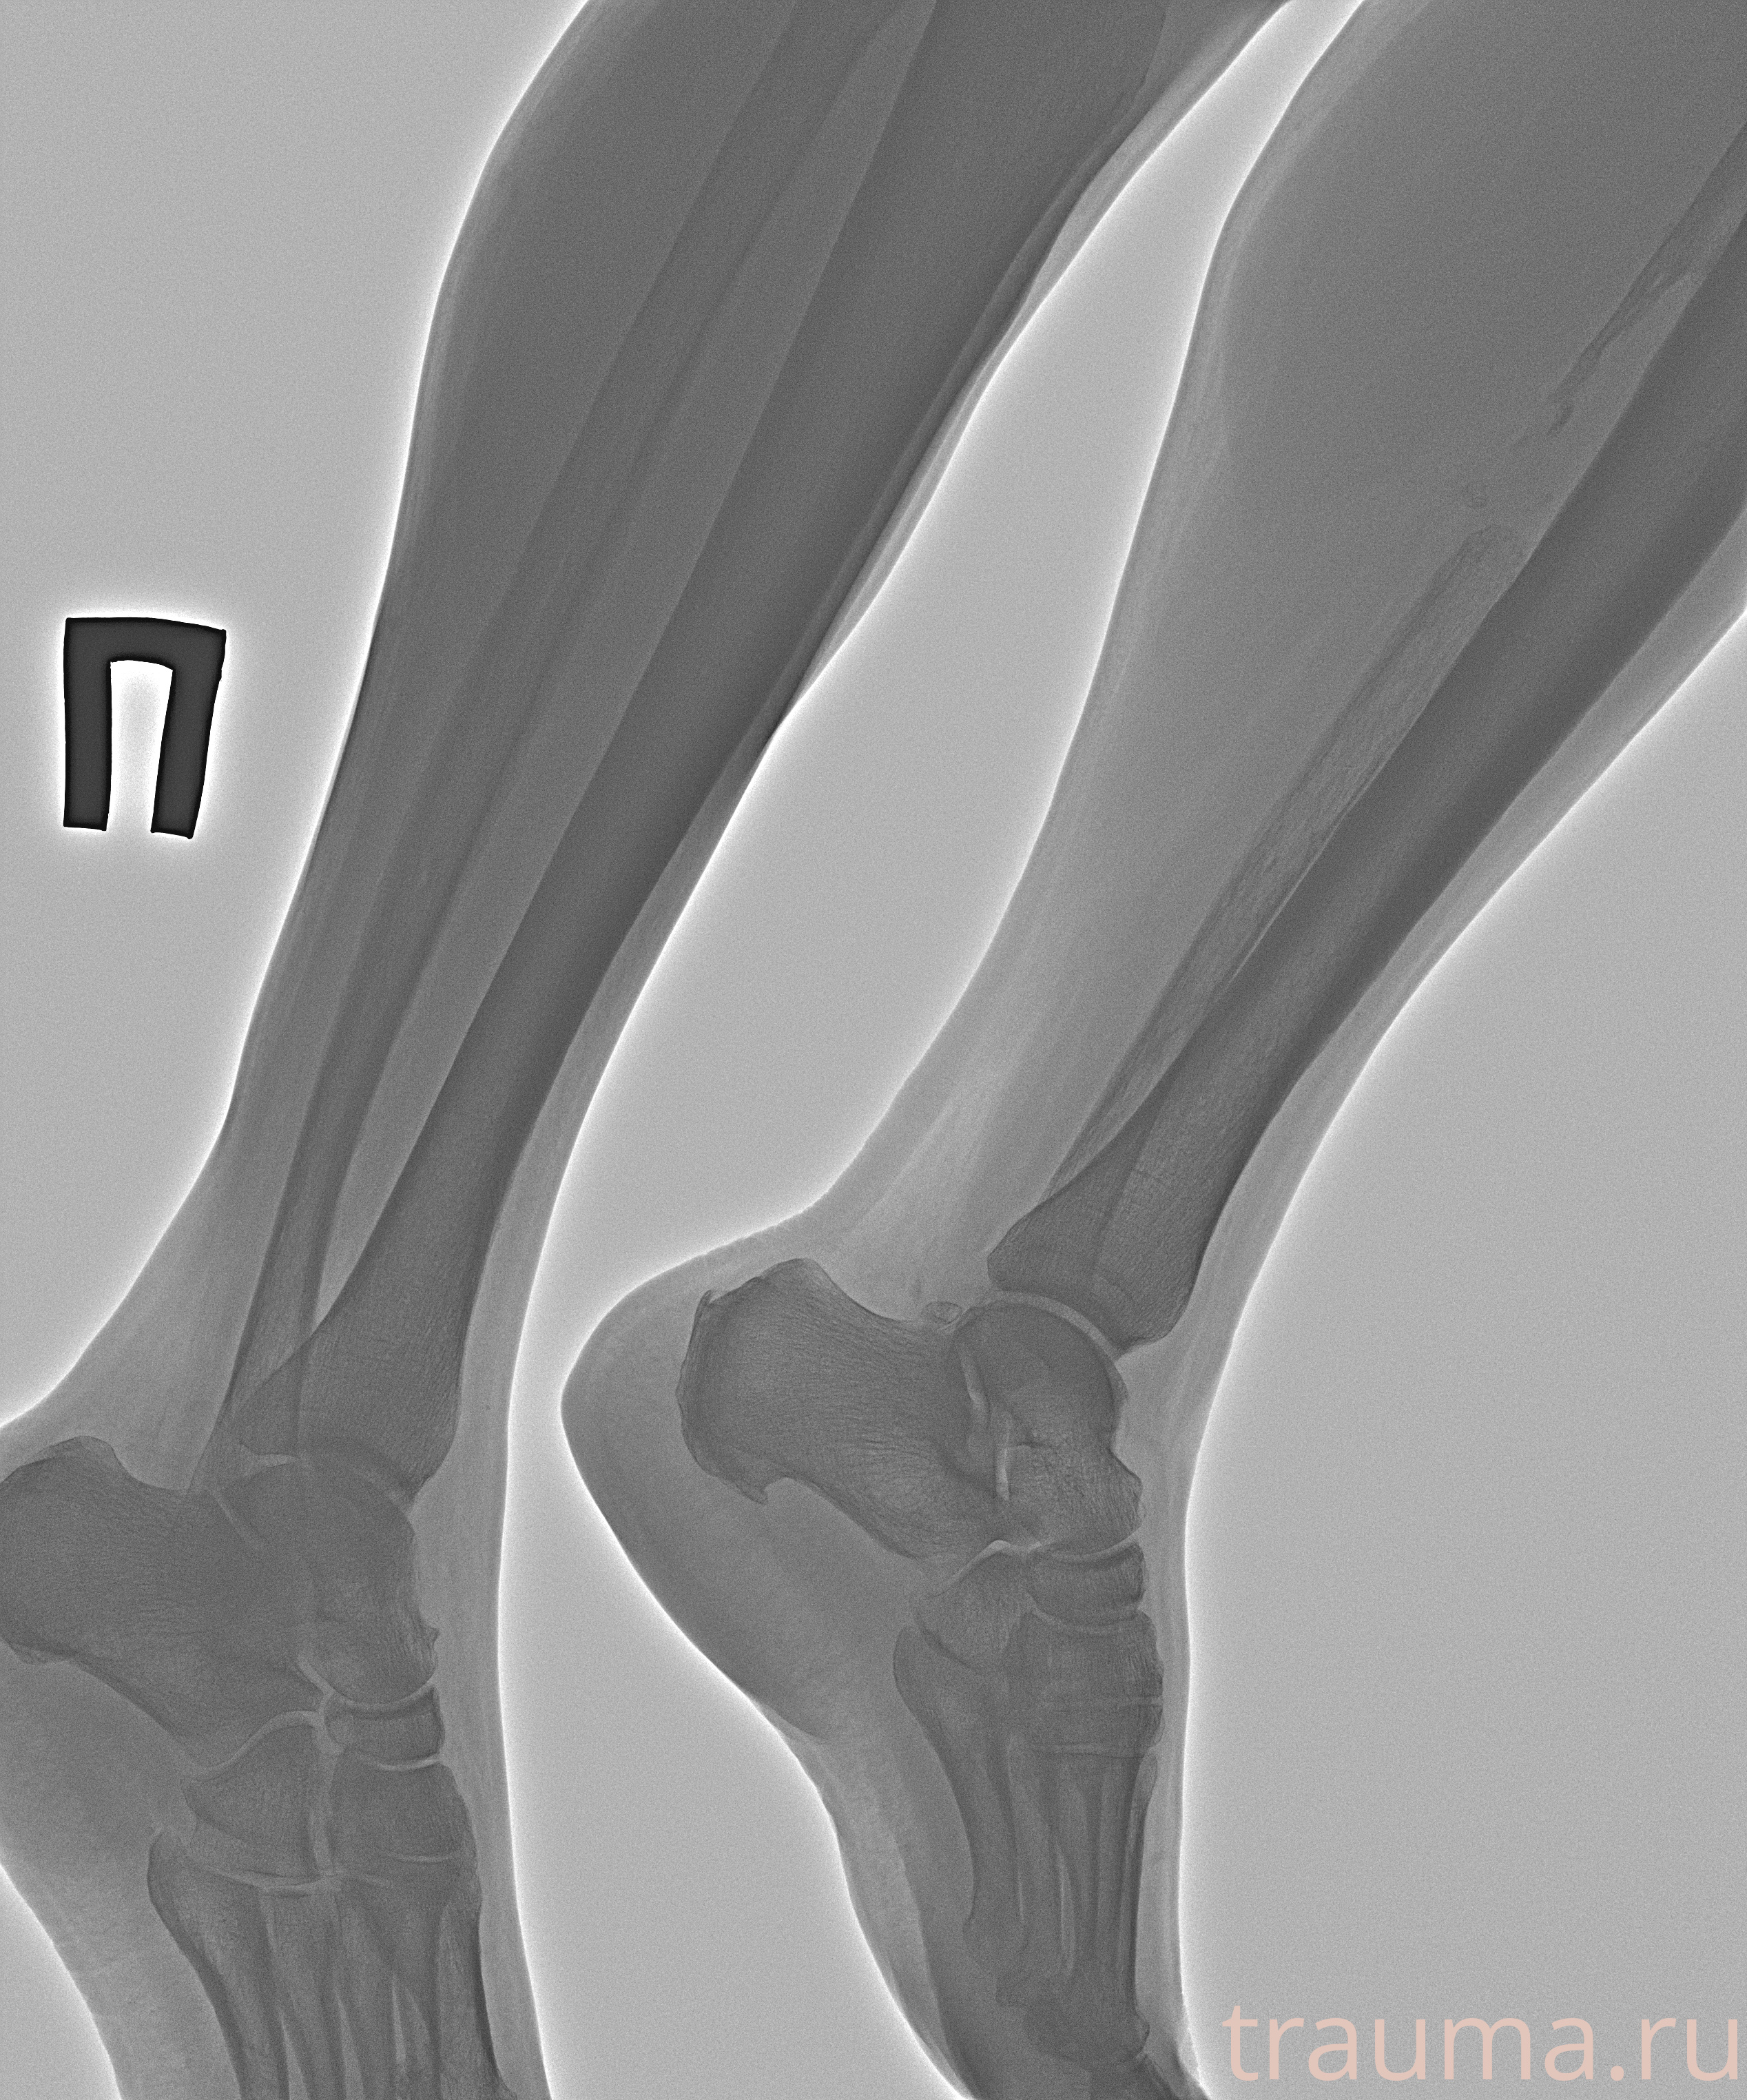

Рентгенограммы

Рентген на дому: по вашему адресу приезжает врач-рентгенолог, травматолог-ортопед с мобильным рентгеновским аппаратом, проводит диагностику травмы или заболевания, делает необходимые рентгенограммы, дает рекомендации по дальнейшему лечению. Получить качественные снимки в домашних условиях возможно благодаря уникальной методике, разработанной МосРентген Центром для института  Склифосовского

Яркость: 1   Контраст: 1   Инвертировать: 0 Увеличение: 1

Перетаскивайте мышь вверх/вниз для контраста, влево/право для яркости. Прокрутка колесом изменяет масштаб. Нажмите Сбросить для возврата к исходному изображению. При увеличении держите мышь в той области, которую хотите рассмотреть.